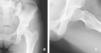

El pinzamiento femoroacetabular es una entidad patológica que se presenta en las consultas del aparato locomotor y que cursa con dolor e impotencia funcional de la cadera en el adulto joven. Se produce por un conflicto de espacio entre el componente femoral y el anillo acetabular en determinadas posiciones de la cadera. El origen puede estar en un defecto en la unión cabeza-cuello femoral, en un exceso de cobertura de la parte anterolateral del acetábulo o en ambas. Se desencadena un atrapamiento entre la unión cabeza-cuello y el reborde acetabular, que conducirá a una lesión inicial en la unión condrolabral y cuya evolución, si no se corrige, produce una degeneración precoz de la articulación.

Femoroacetabular impingement is a new pathological entity that is becoming more frecuently recognized in consults related to locomotor system. It appears when, due to a malformation in the femoral neck-head junction, a relative excess of bone in the anterolateral part of the acetabullum or both conditions together, a impingement is developed during the arc of movement of the joint, resulting in an initial chondrolabral lesion, being source of symptoms and functional impairment in the young patient. In case of no correction it will probably leads to secondary osteoarthritis when the cartilage lesion progress.